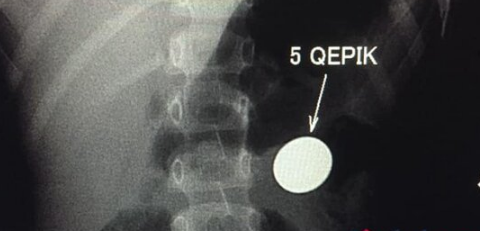

Bakıda 4 yaşlı uşaq ehtiyatsızlıqdan qəpik udub. Müayinə zamanı qəpiyin təbii yolla mədədən xaric edilməsinin mümkünsüz olduğu məlum olub.

"Bir həftə qabaq 4 yaşında uşaq 5 qəpik udub. Bir həftədir qəpik uşağın mədəsindən ifraz olunmur. Gətiriblər müayinəyə, biz də aşkar etdik ki, qəpik hələ mədədir. Mədənin çıxacaq hissəsi uşaqlarda dar olduğuna görə çıxmır. Qəpiyin diametri mədənin çıxacaq hissəsinin diametrindən iki dəfədən çox böyükdür. Ona görə mədədən keçmədi, qalıb mədədə. Biz məsləhət gördük ki, endoskopiya müayinəsindən keçsin, endoskopik yolla çıxartsınlar. Hələ bir xəbər yoxdur. Qəpik uşağın mədəsindən çıxarılacaq".